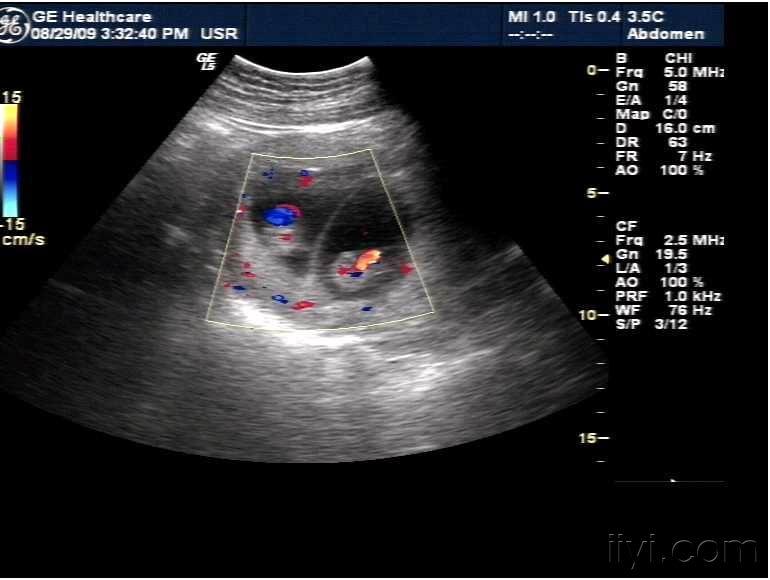

双卵双胎,双绒双羊是龙凤胎图片

双卵双胎的介绍

双绒双羊是龙凤胎图片

怀龙凤胎两个孕囊图片